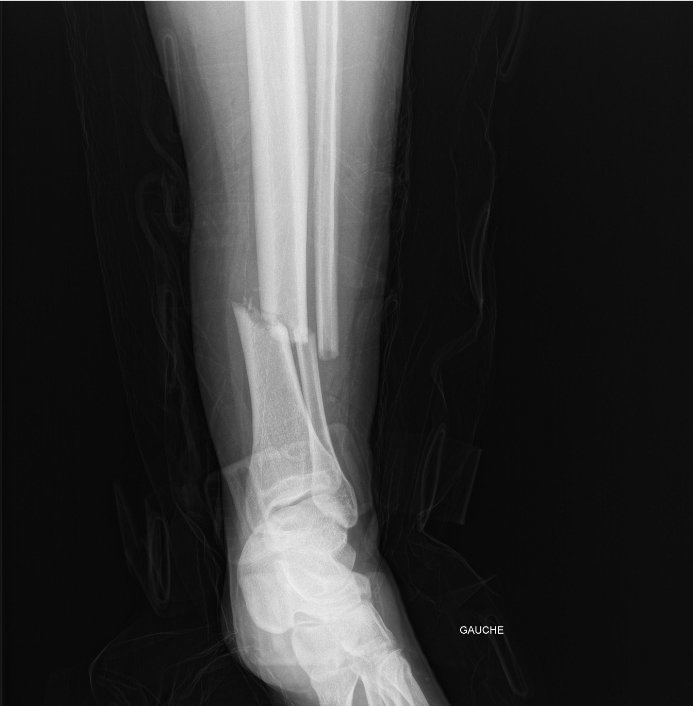

Double fracture du tibia péroné, des questions ?

Je me suis fait ça aujourd'hui dans l'aprèm

chute en moto

la moto qui tombe pleinement sur la jambe gauche

Accident en moto à la con, j'ai mal négocié un virage en descente et j'ai freiné trop fort, j'ai basculé par dessus la moto et elle m'a écrasé la jambe.

La jambe bien droite, la pente + la moto de 300kg qui tombe dessus, ça pardonne pas :)